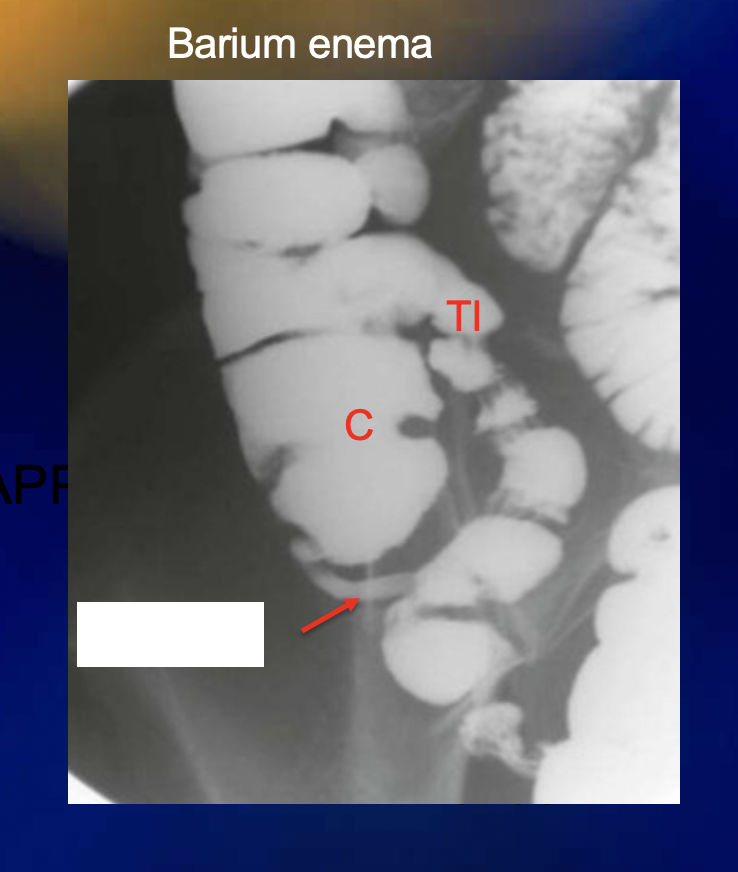

What is the purpose of giving barium sulfate in xray?

What does barium look like on xray or CT?

White

If a person has appendicitis and their appendix is retrocecal, they will likely present with […] pain

If a person has appendicitis and their appendix is pelvic, they will likely present with […] pain

The appendix is [….]peritoneal

Intra